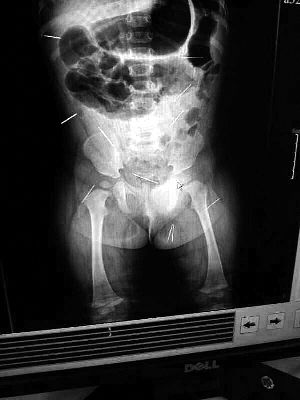

山東聊城11個(gè)月女?huà)胼孑妫ɑ┮伤票蝗艘?2根鋼針插滿臀部、腹腔等部位,昨天在兒童醫(yī)院會(huì)診后,醫(yī)生稱3根針靠近胸腔最危險(xiǎn),首批先行取出,預(yù)計(jì)將在下周二手術(shù)。孩子父母稱孩子一直由家人照顧,自家與他人并無(wú)冤怨。山東警方表示正在偵破中,不便透露案情。

“要不是當(dāng)初那幾個(gè)紅點(diǎn),可能到現(xiàn)在我們還不知道孩子身體里有鋼針!”昨天,在兒童醫(yī)院住院處,萱萱爸爸范先生稱,日前原本很愛(ài)笑的萱萱突然變得有些焦躁,一抱起來(lái)就哭,孩子母親偶然間在萱萱屁股上發(fā)現(xiàn)了幾個(gè)小紅點(diǎn)兒,原以為是蚊蟲(chóng)叮咬,就醫(yī)結(jié)果卻讓人不寒而栗?!搬t(yī)院拍出的片子上,萱萱的體內(nèi)有12根鋼針,插滿臀部、腹腔、骨盆等各個(gè)部位?!狈断壬榻B,因?yàn)殇撫樢焉钊塍w內(nèi),要是孩子不哭鬧,他們很難發(fā)現(xiàn)。

北京晨報(bào)記者了解到,目前體內(nèi)的12根鋼針多分布在孩子的臀部,一根在腹部,其余3根在胸腔附近,其中一根很接近心臟?!耙?yàn)楹⒆犹?,醫(yī)生們害怕取針的時(shí)候?qū)λ斐蓚Γ谛厍桓浇?針可能會(huì)威脅她的生命”。